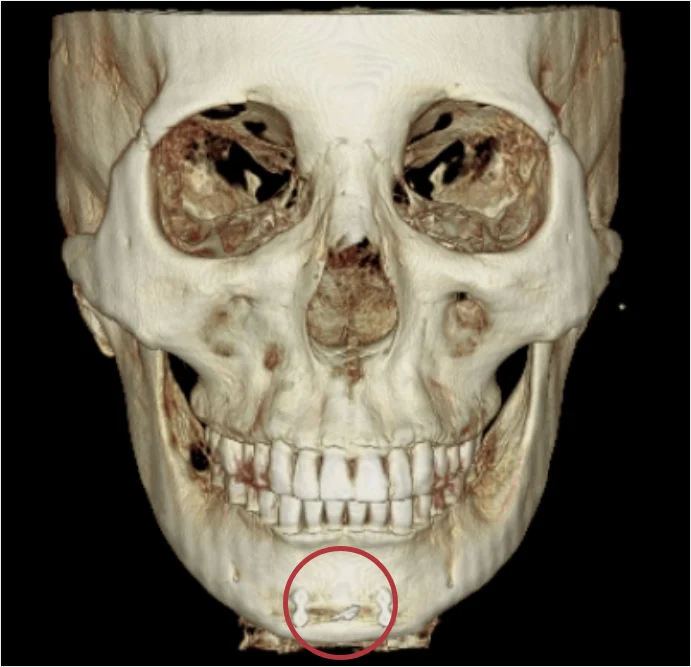

可以清楚確認嵌入在下顎與顴骨部位的金屬固定釘。

透過 CT 掃描精確確認金屬固定釘位置